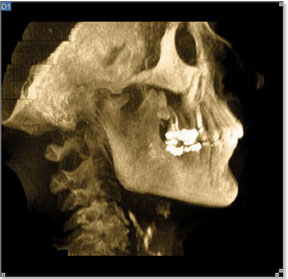

The CT scan of the right TM Joint produced a startling revelation. A large boney projection extended from the anterior condylar neck of the mandible superiorly, like a tree trunk, and mushroomed up to the opposing articular eminence. A 3-D projection showed the growth wrapped from posterior, to beneath, and even anterior to the articular eminence. This explained the inability to translate upon opening. A panoramic view also clearly showed the hard tissue pathological projection, which extended vertically beyond the height of the mandibular condyle, thus producing a resulting right side open bite. The diagnosis was quickly clarified through CBCT technology.